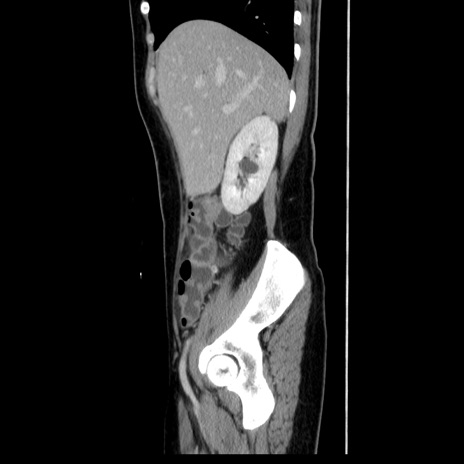

症例39(矢状断像)

【症例】40歳代女性

【主訴】上下腹部痛

【現病歴】2日目から下腹部痛あり。夜間は痛みで眠れなかった。昨日より上腹部痛と下痢が出現。臥位で痛みは軽快したため、休んでいた。本日になって臥位でも立位でも痛みが強くなってきたため救急要請。

【既往歴】子宮内膜症

【身体所見】部:平坦・軟、左上下腹部に圧痛あり、反跳痛あり。

【データ】WBC 21800、CRP 26.78

CT